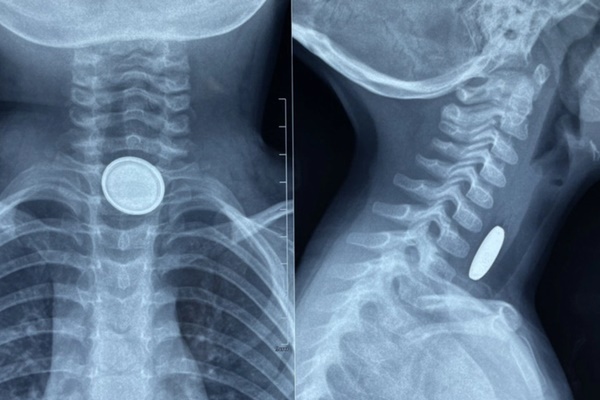

Dị vật là viên pin điện tử hình cúc áo có đường kính 20mm được gắp ra ngoài thành công, kiểm tra tại vị trí viên pin mắc lại đã có hiện tượng bỏng thực quản.

Nếu dị vật bị hóc là pin Lithium, có đường kính trên 20mm sẽ dẫn tới những tổn thương thực quản nặng nề hơn. Do đó, việc xác định kích thước và chủng loại pin cũng như thời gian hóc rất có ý nghĩa trong việc tiên lượng bệnh.